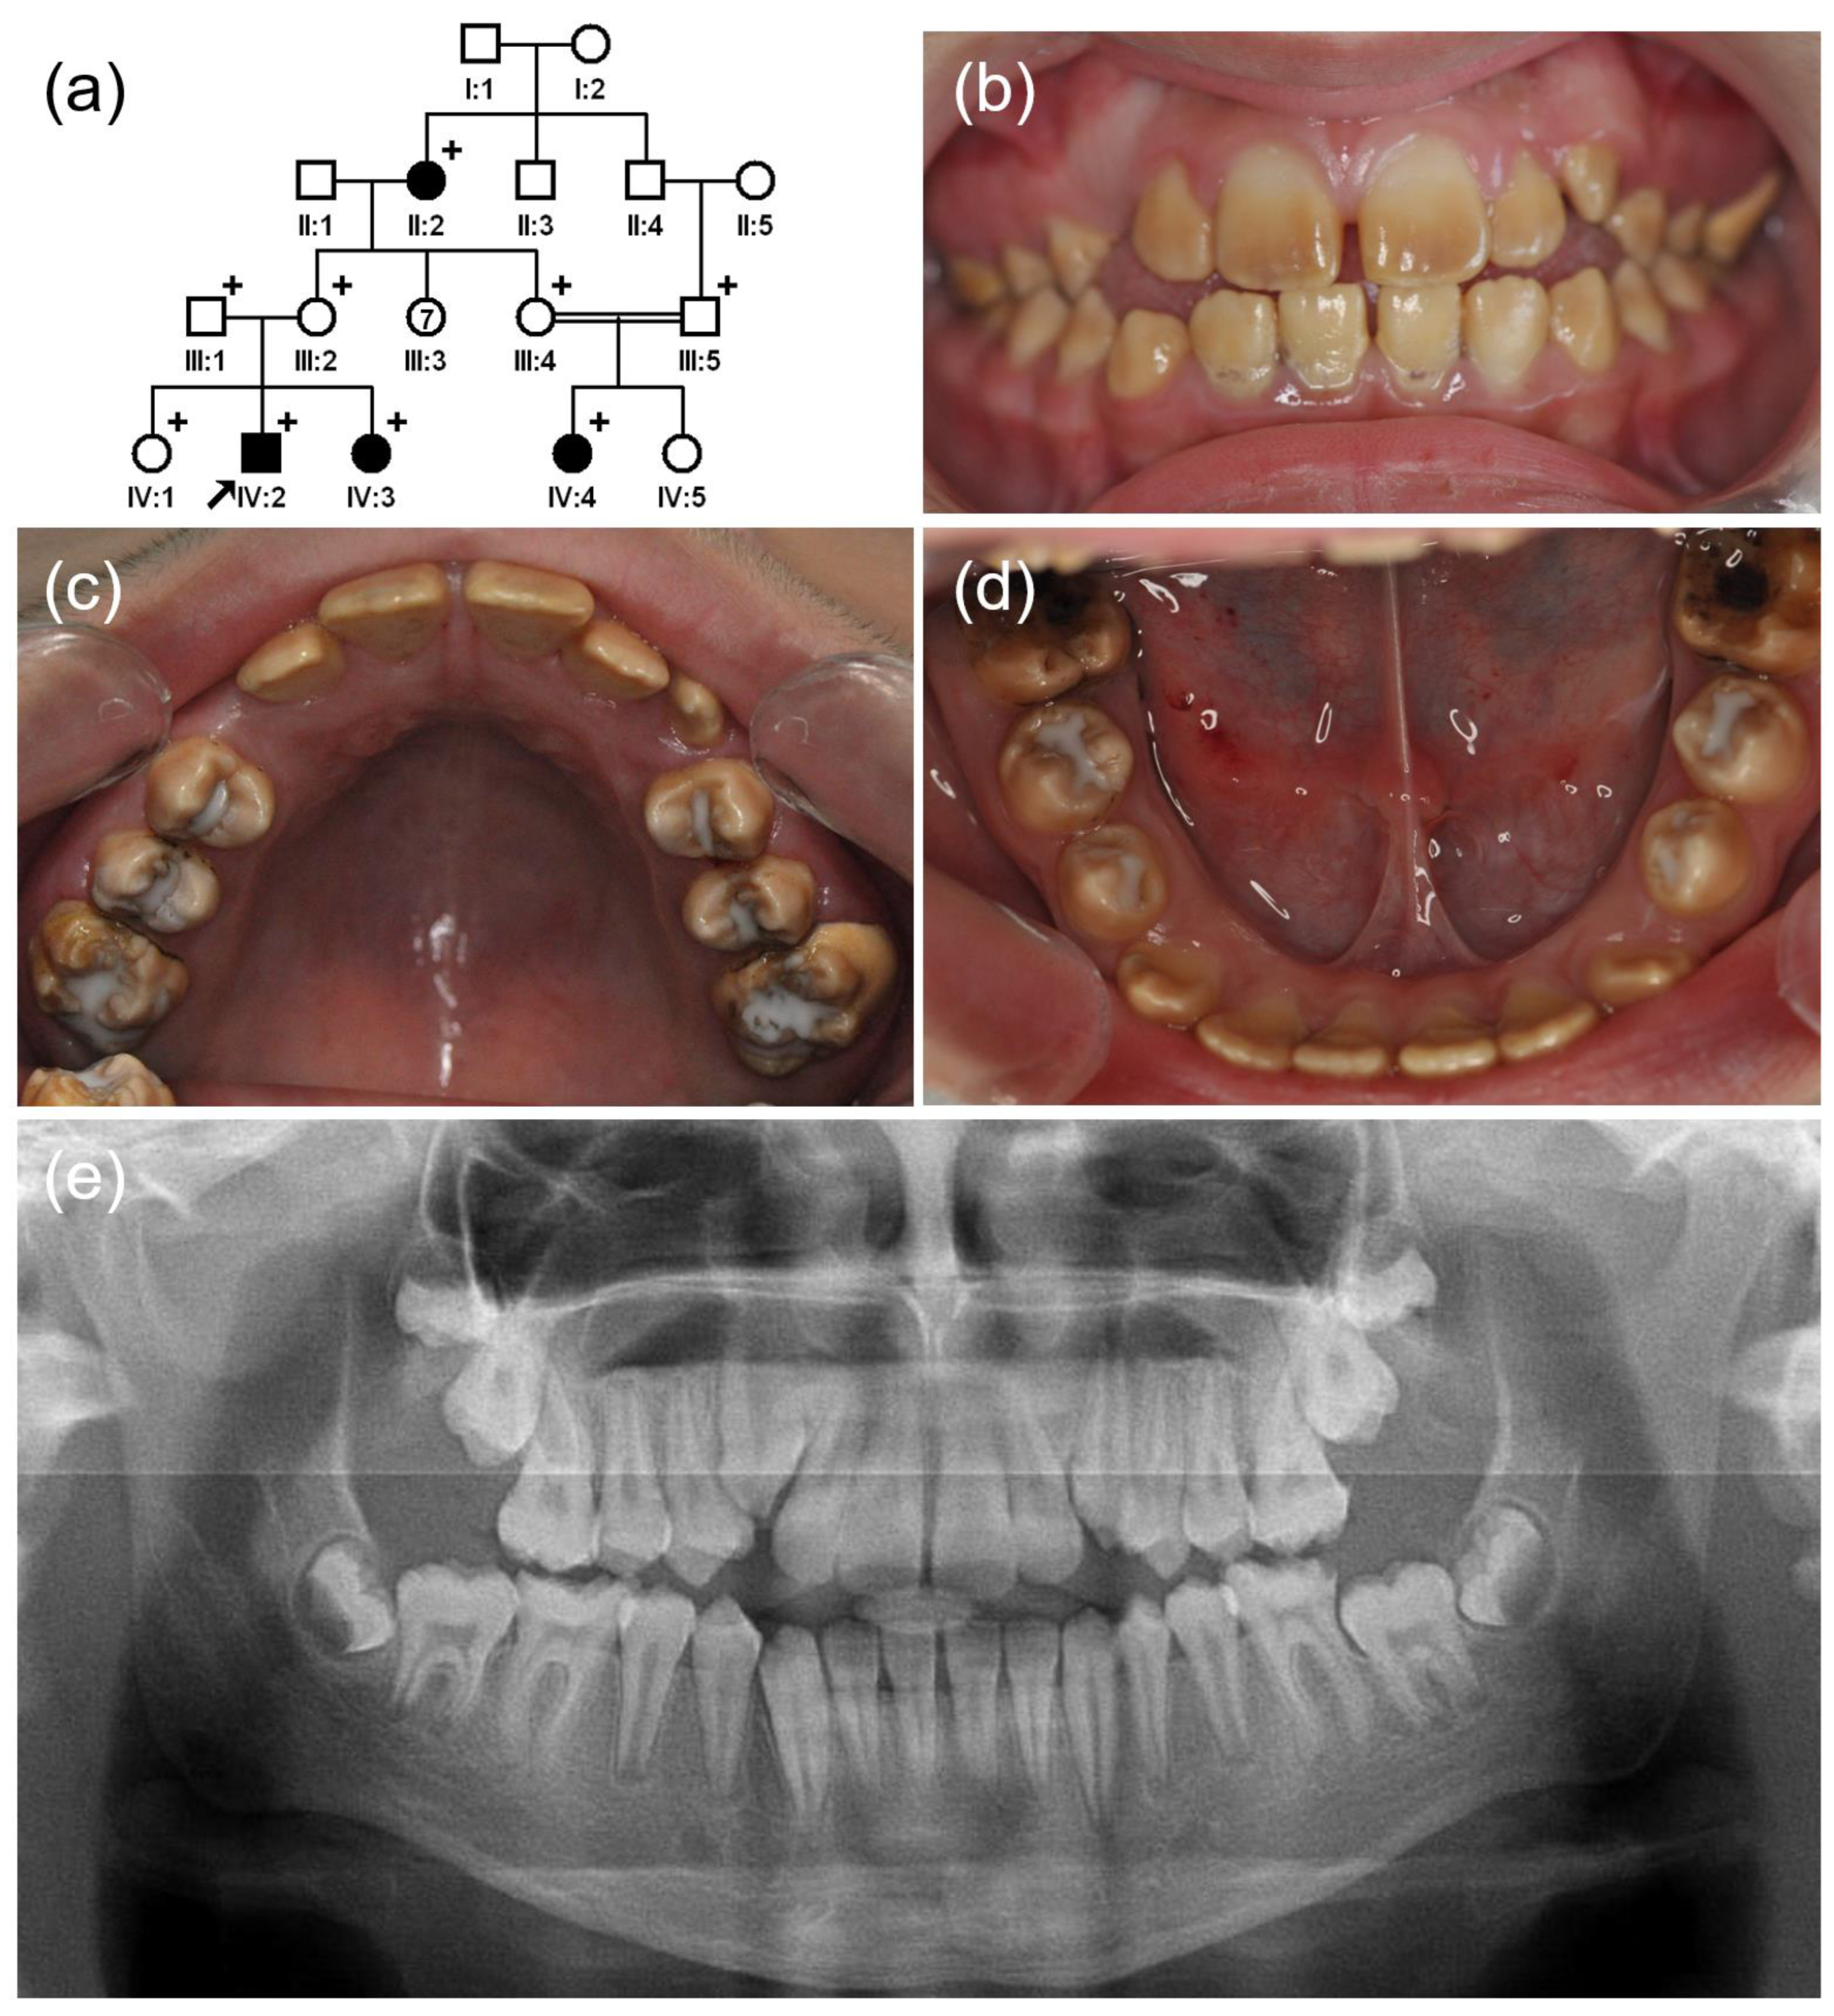

3.2. Family 2